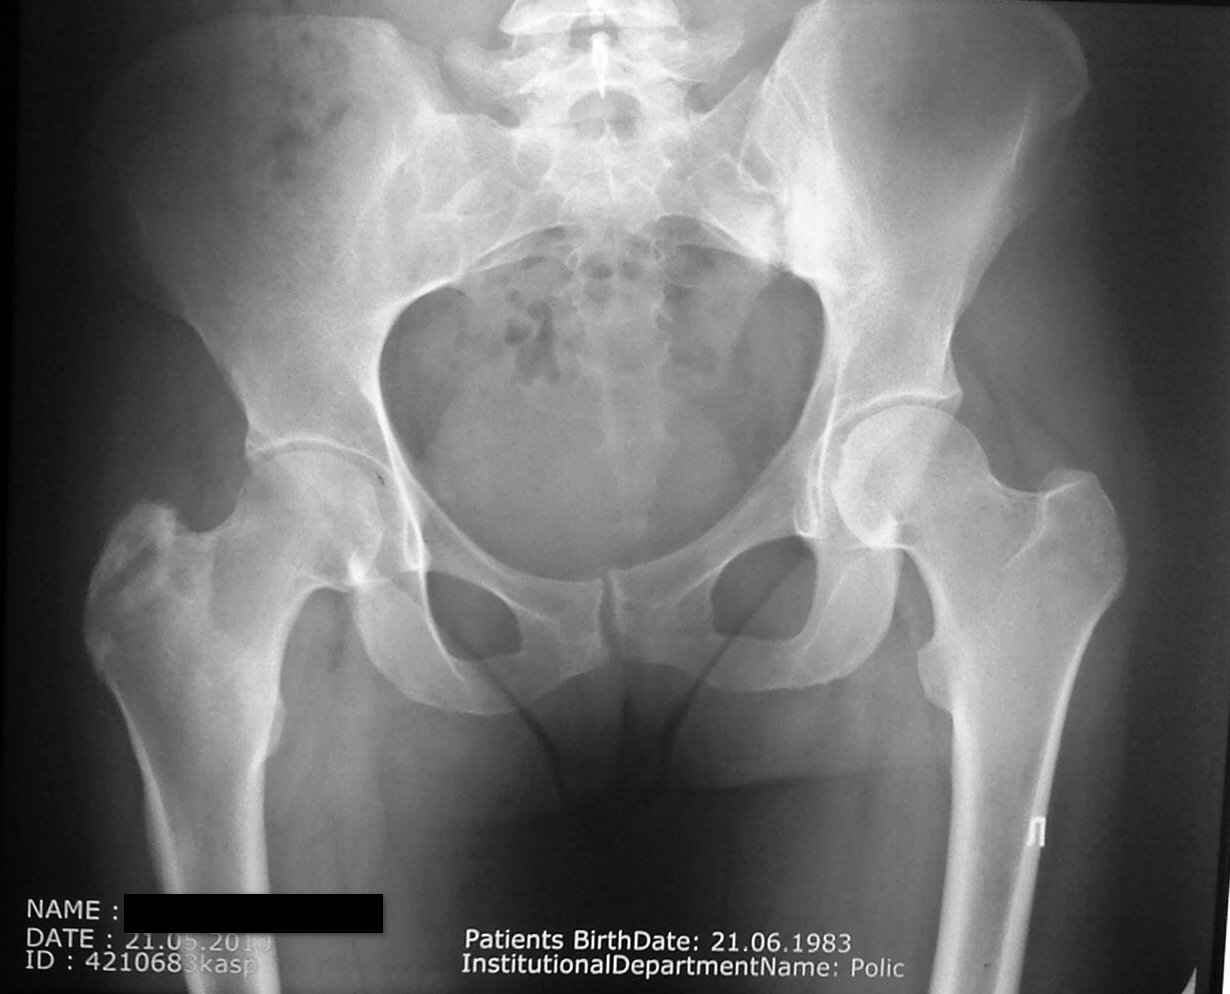

Уважаемые коллеги хотелось бы узнать ваше мнение по поводу рентгенограмм пациентки.

Ко мне на приём обратилась женщина 27 лет с жалобами на

незначительные боли и выраженное ограничение движений в тазобедренном суставе. С её слов

ситуация развивалась постепенно на протяжении 7-10 лет. клинически имееется выраженное

ограничение движений в тазобедренном суставе(равномерно все виды движений). Буду рад

любому мнению и по мере лабораторного дообследования сообщу о его результатах.